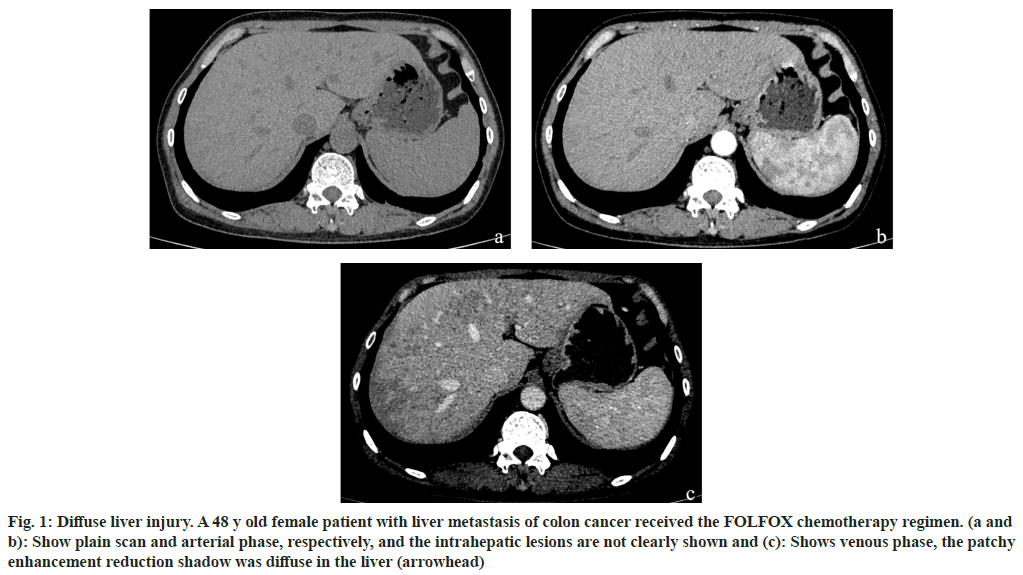

Among the 170 patients with liver injury after chemotherapy, the FOLFOX regimen accounted for the highest proportion of liver injury cases, accounting for 51 % of cases. This was followed by FOLFOXIRI, cetuximab+FOLFOXIRI, bevacizumab+FOLFOXIRI, and bevacizumab+FOLFOX, which accounted for 26 %, 9 %, 9 % and 5 %, respectively as shown in Table 2. The imaging findings of the 170 patients were divided into diffuse (fig. 1), local (fig. 2) and small focal (fig. 3). The different chemotherapy regimens showed that 77 of the 87 cases of FOLFOX showed diffuse liver injury, accounting for approximately 88.5 % of the chemotherapy regimen. Among the 45 cases of the FOLFOXIRI regimen, 43 cases showed local liver injury, accounting for approximately 95.6 % of the chemotherapy regimen. A total of 38 cases were treated with three regimens of cetuximab+FOLFOXIRI, bevacizumab+FOLFOXIRI, and bevacizumab+FOLFOX. Of these, 36 cases showed small focal liver injury, accounting for 94.7 % of the chemotherapy regimen as shown in Table 3.

Fig. 1: Diffuse liver injury. A 48 y old female patient with liver metastasis of colon cancer received the FOLFOX chemotherapy regimen. (a and b): Show plain scan and arterial phase, respectively, and the intrahepatic lesions are not clearly shown and (c): Shows venous phase, the patchy enhancement reduction shadow was diffuse in the liver (arrowhead)